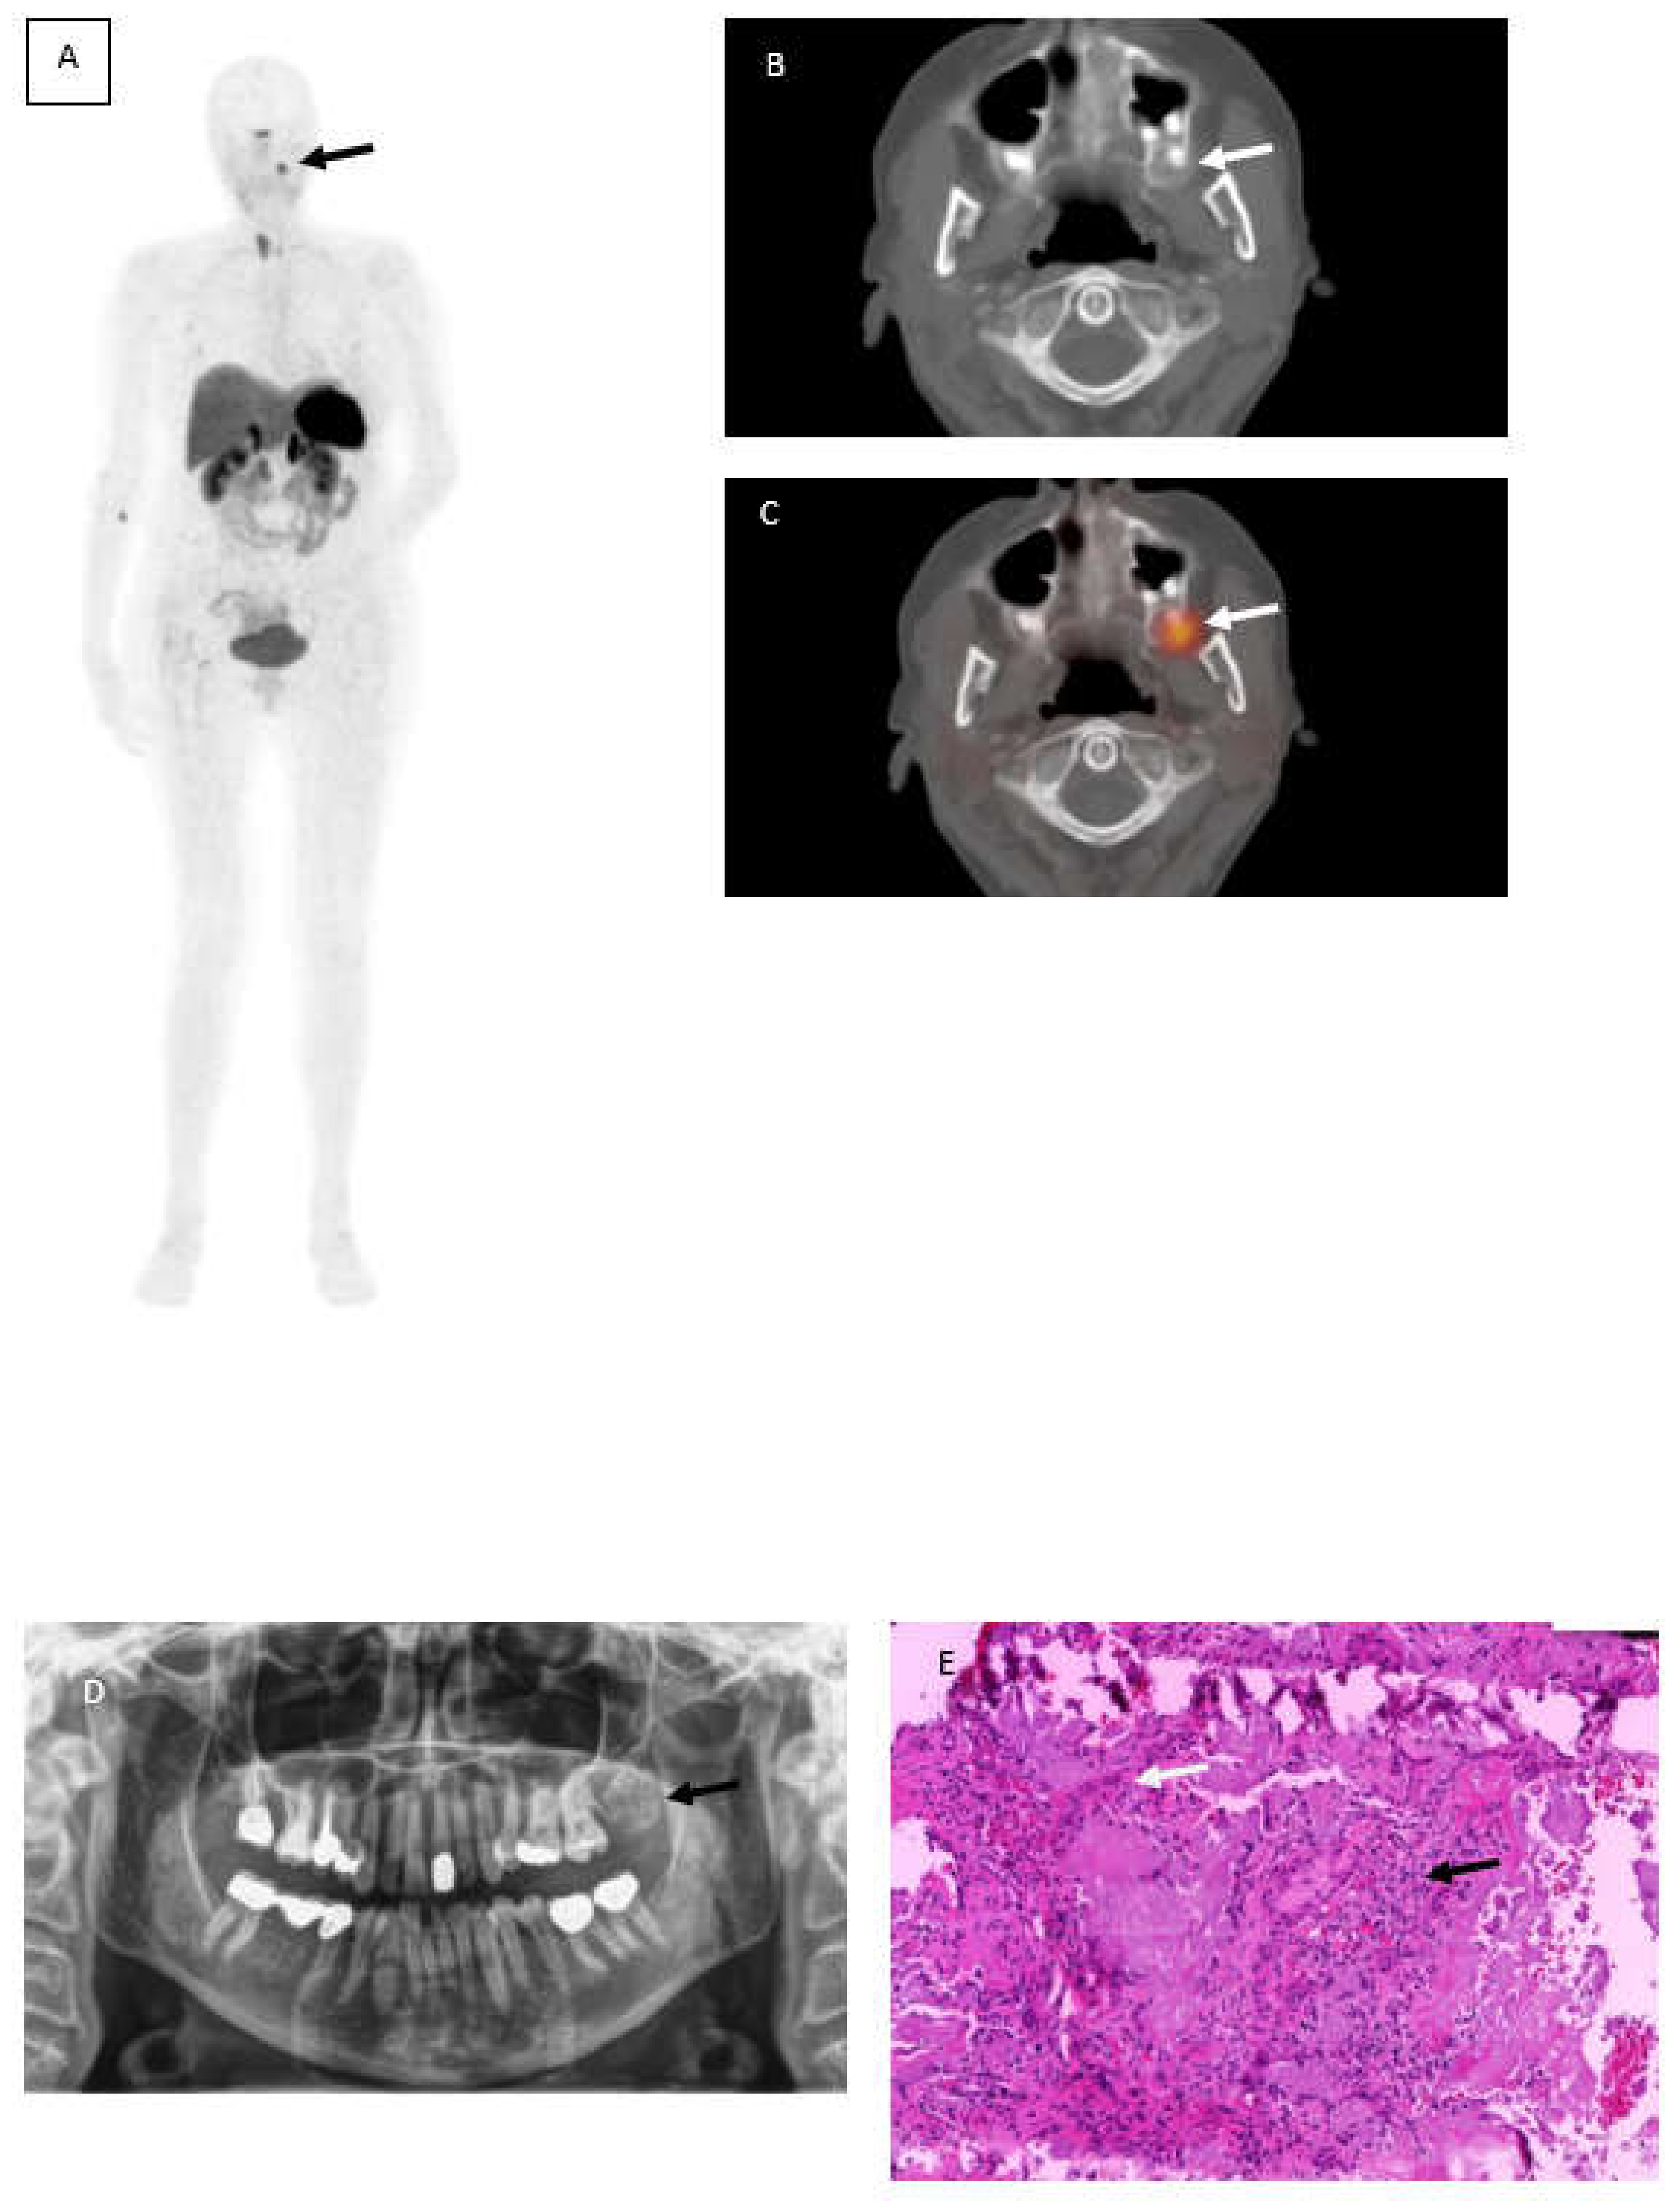

Pindborg Tumor—An Uncommon Odontogenic Tumor Detected by 68Ga-DOTATOC

Herden, A.; Sabtan, D.; Warnecke, K.; Doll, C.; Furth, C. Pindborg Tumor—An Uncommon Odontogenic Tumor Detected by 68Ga-DOTATOC. Diagnostics 2022, 12, 389. https://doi.org/10.3390/diagnostics12020389